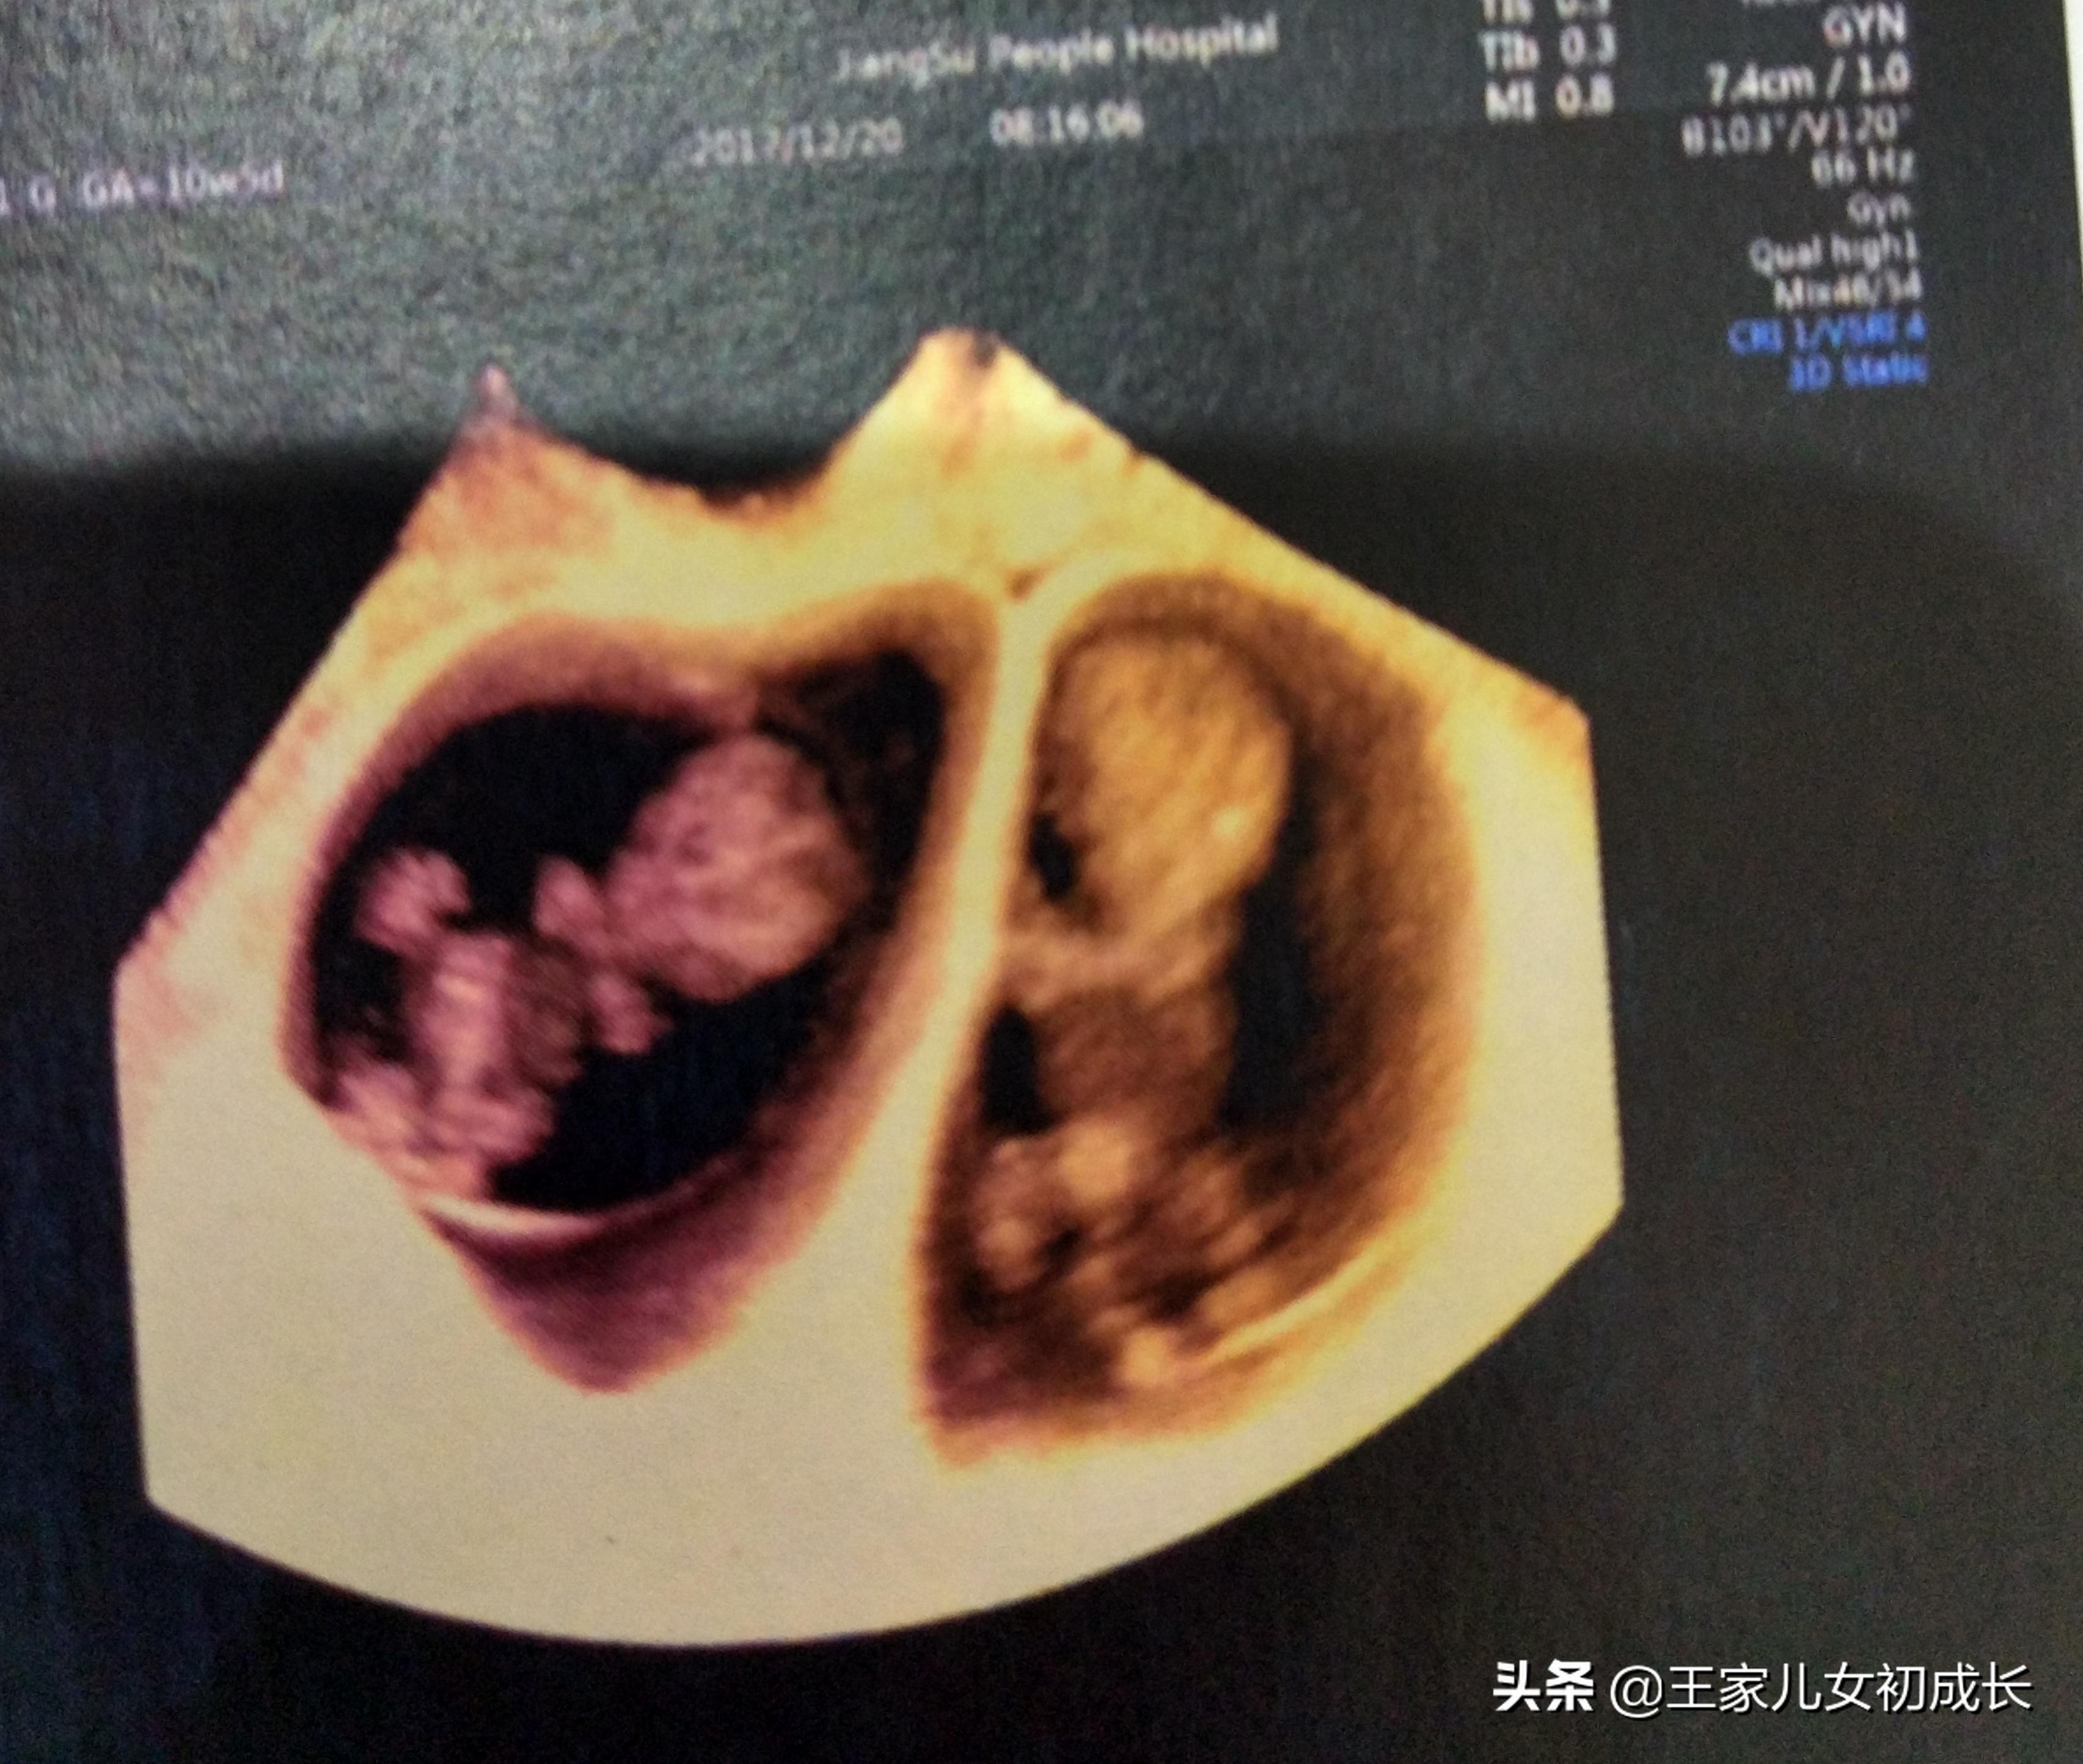

促排我之所以说他是最黑暗的日子,是因为这十几天期间,除了每天要打不同的3种药物之外,还要不断的来医院监测B超抽血测激素情况,然后医生根据这两项数据不断的调整用药剂量。我住所离医院大概1小时的路程,每次来医院都要在7点左右到,这就意味着早上都要6点不到爬起来,每一项检查都得要排队。每一次的数据都牵动着我的玻璃心:卵泡是不是少了、大小是不是长慢了,激素浓度是高了或是低了,子宫内膜厚度正不正常。

取卵前B超显示我只有8个卵泡了,我有点伤心的,我基础卵泡一共13个,经过这一段时间的生长和淘汰,只剩下8个了,一起的姐妹有20多个的,有十多个的,像我这8个绝对属于数量较少的。那会子就是觉得,泡泡多机会就多,心里还有点责怪医生是不是给我用药计量有问题,咋就还剩8个了呢,特别的玻璃心,任何一个数字有波动,心里都要胡思乱想一番的。取完卵后更伤心,只取了7个可爱的泡泡小宝贝了……